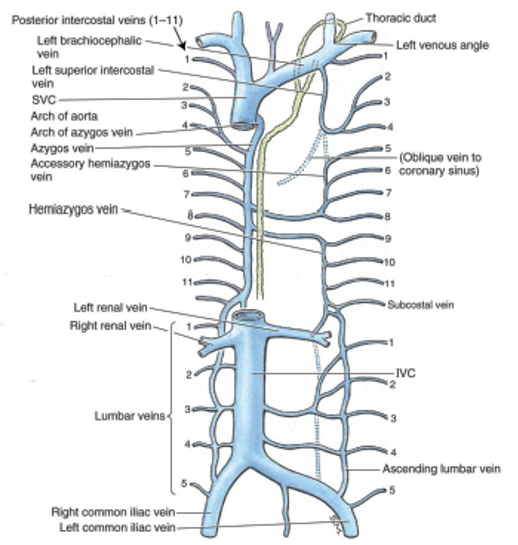

point out the azygos vein, the accesorry hemi-azygos vein and the hemi-azygos vein?

the azygos vein is on the right side under the big "faucet" going up

you can see a divit on the left side where the accessory hemi and hemi azygos travel behind and into the right side

the accessory hemi-azygos vein is the vein on the left side connecting the intercostal spaces from above the divit (on top)

the hemi-azygos vein is below the divit (on bottom)

overall, the "azygos system":

- drains what 2 things?

- consists of what 3 veins?

- “azygos system” also receives blood from where?

- this system acts as “collateral pathway” to “bypass” what?

the back & thoracoabdominal walls

azygos, hemi-azygos and accessory hemi-azygos veins

trunk and lower extremities

the IVC (inferior vena cava)

accessory hemi-azygos vein:

- receives blood from ______________ intercostal spaces

- Accessory hemi-azygos vein crosses midline and drains into where?

- NOTE: left side 1st – 4th intercostal spaces drain directly into where?

left side 5th - 8th

the azgos vein

left brachiocephalic vein

look at picture

hemi-azygos vein:

- receives blood from where?

- also receives blood from what other 2 left places?

- Hemi-azygos vein crosses midline and drains into __________?

left side 9th - 11th intercostal spaces

abdominal/pelvic trunk and lower extremity

azgos vein

look at picture

how is the lumbar veins a plan B?

they are a plan B in case there is some sort of obstruction in the inferior vena cava

(look at ascending lumbar vein in picture)

what do the right and left common illiac veins take care of?

the legs

azygos vein:

Receives blood from what 3 places?

Azygos veins continues on to drain into the ___________?

right side intercostals

hemiazygos & accessory hemiazygos veins

also receives blood from right abdominal/pelvic trunk and lower extremity

SVC (superior vena cava)

notice how it gets blood from the hemi azygos and accessory azygos and how it travels up into the SVC